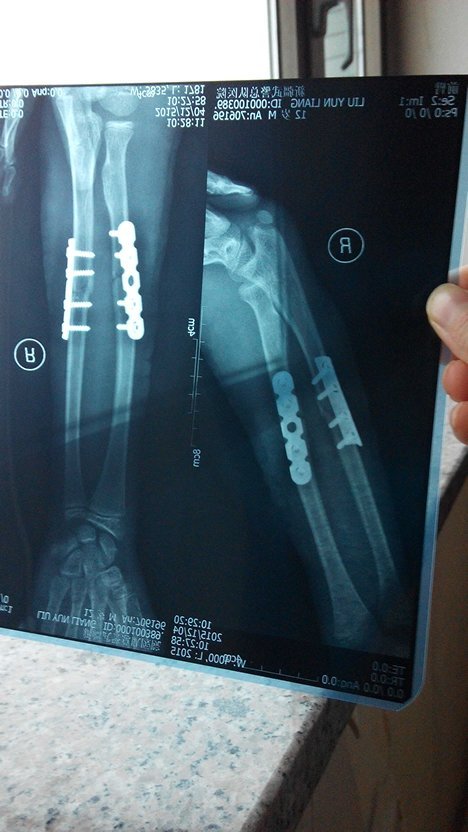

孩子在学校走廊被同学绊到骨折并做手术 对方应怎样赔偿